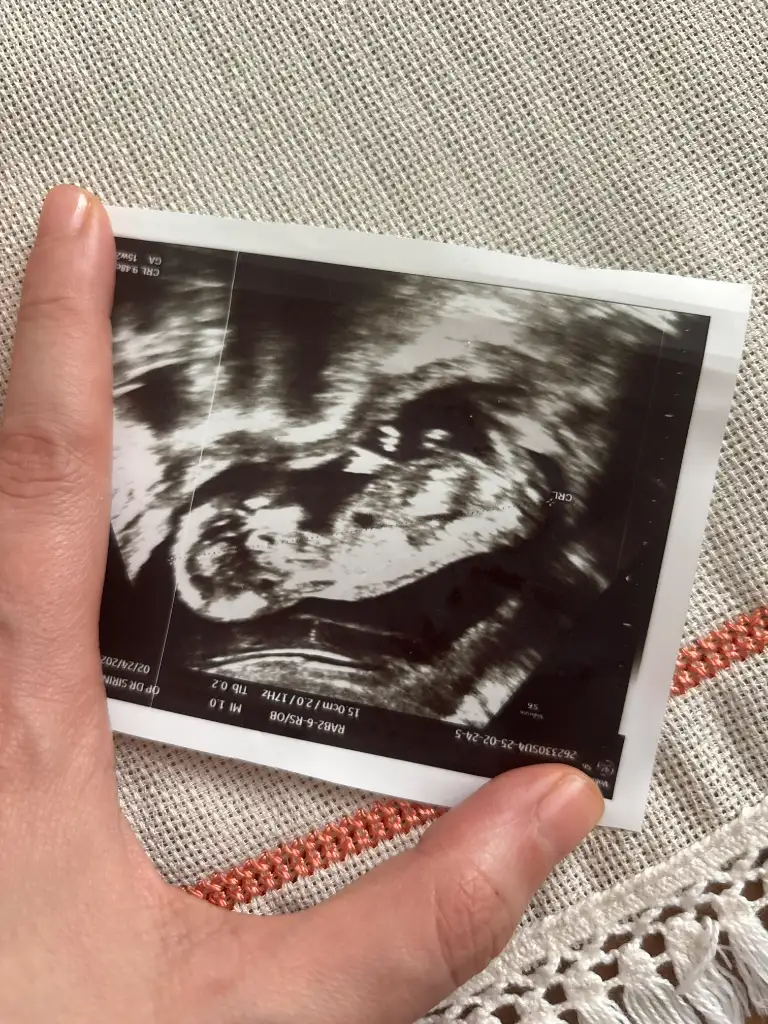

13 haftalik bakarmisiniz nedir sizce